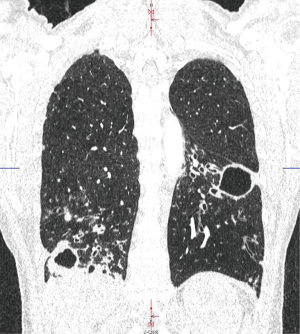

By far and large, the most common symptom in bronchiectasis is chronic, productive cough (16,19), which was observed in 85% of our patients, often accompanied by copious amounts of expectorations (56% in our collective). Even though we had a high rate of patients presenting with hemoptysis (24%) presenting clinical symptoms were well in line with most other tertiary outfits (15). Due to tenacious investigations by our referring pneumologists, we were able to identify a cause for bronchiectasis in 53% of all patients admitted for surgery, which is slightly beyond results obtained by other groups (15): according to published data, underlying pathologies are discovered in less than 40% admitted for treatment (8,16). This may be attributable to our systematic work-up: As per protocol, all our patients underwent lung function testing, standard X-ray and HRCT. Even a 10-mm slice-thickness HRCT is sufficient to determine distribution and severity of disease with a sensitivity of 66% and a specificity of 92% (20). Additional bronchoscopy was always performed as well to rule out foreign bodies or endobronchial masses that may cause bronchiectasis. In-depth examination of our patients past medical history confirmed documented chronic infectious disease in more than 50% of cases. As a regional referral center for NTM-disease, which can be associated with bronchiectasis, we treated a certain number of patients with this pathology. NTM can be divided into two subgroups radiologically, a fibrocavitary and a nodular/bronchiectatic type (21), with the latter being almost impossible to discern from post-infectious bronchiectasis colonized by NTM (22). Despite overlapping clinical features with conventional non-CF-bronchiectasis, NTM-management is particularly complex and a surgical approach may be viable to induce treatment success through removal of septic lung portion allowing drug therapy discontinuation, symptomatic treatment of hemoptysis, or partial resection in advanced cases to slow down overall disease progression (Figure 2) (23). Our 2 included cases of NTM were referred to surgery for complete resection of all infectious sites, in one case by bilateral procedures.